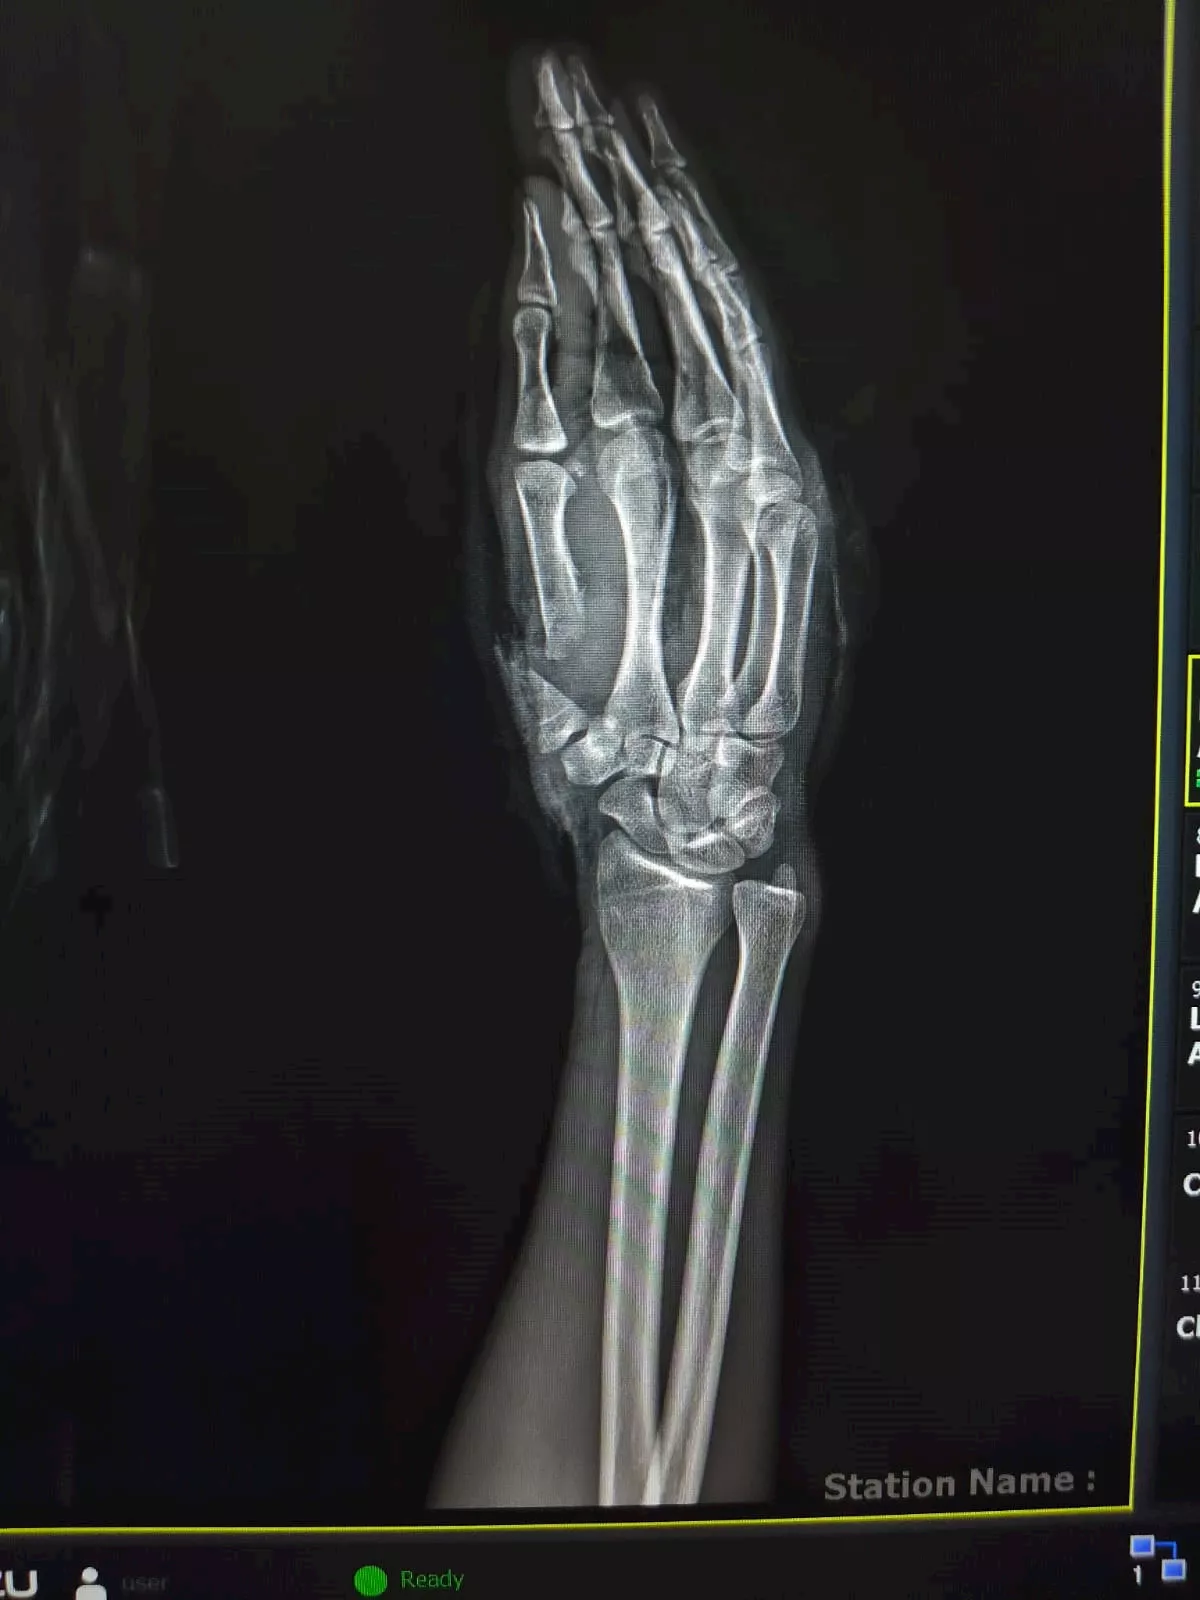

نجح فريق طبي متخصص بوحدة الجراحات الميكروسكوبية بمستشفى جامعة سوهاج في إنقاذ شاب يبلغ من العمر 26 عامًا، تعرّض لبتر كامل في إصبع الإبهام لليد اليمنى، وقطع كامل بالشرايين والأوردة، إثر اعتداء عليه بسلاح أبيض "ساطور".

ومن جانبه، أكد الدكتور مجدي القاضي، عميد كلية الطب البشري ورئيس مجلس إدارة المستشفيات الجامعية، أن الفريق الطبي نجح في إعادة زرع إصبع الإبهام باستخدام جراحة ميكروسكوبية دقيقة استغرقت نحو 6 ساعات، تم خلالها توصيل الشرايين والأوردة والأعصاب المغذية للإصبع، فضلًا عن تثبيت عظامه باستخدام أسلاك معدنية، ما أسهم في استعادة الدورة الدموية واستقرار الحالة.

وفي السياق ذاته، أوضح الدكتور ياسر عثمان، مدير وحدة الجراحات الميكروسكوبية، أن الشرايين والأوردة والأعصاب استعادت وظائفها الحيوية، وأن حالة المريض مستقرة دون مضاعفات، مع استمرار المتابعة الطبية لضمان التعافي الكامل.